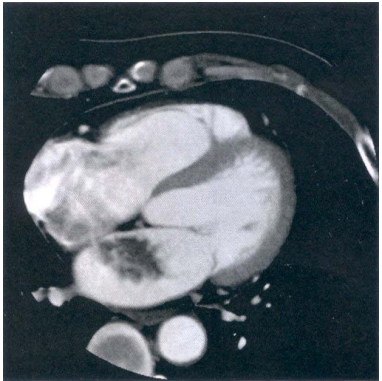

77 53 歲男性,因突發性右膕動脈栓塞就醫,心臟 CT 影像如附圖,則最可能的診斷為下列何者?

(A)左心耳血栓(left atrial appendage thrombi) (B)左心房黏液瘤(left atrial myxoma) (C)二尖瓣狹窄合併左心房血栓 (D)右心房黏液瘤(right atrial myxoma)